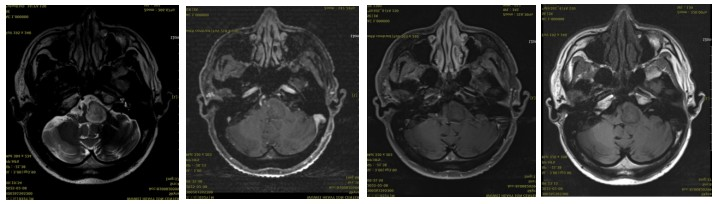

Post-treatment MRI: A space-occupying lesion with enhancement in the right part of the brainstem, accompanied by compression of the adjacent fourth ventricle, showing little change compared to the previous scan (2025-01-10). Efficacy evaluation: SD (Stable Disease).

In this case, the short-term efficacy evaluation of carbon ion radiotherapy for a patient with a malignant medullary tumor was assessed as SD (Stable Disease). The patient's symptoms, such as headache, dizziness, coughing while drinking, nystagmus, right-sided facial paralysis, numbness on the right side of the face, and weakness in the left lower limb, showed improvement compared to their condition at admission. The treatment was well-tolerated, with no significant adverse reactions observed during the course of therapy. This case confirms the efficacy and safety of carbon ion radiotherapy in the treatment of malignant medullary tumors.